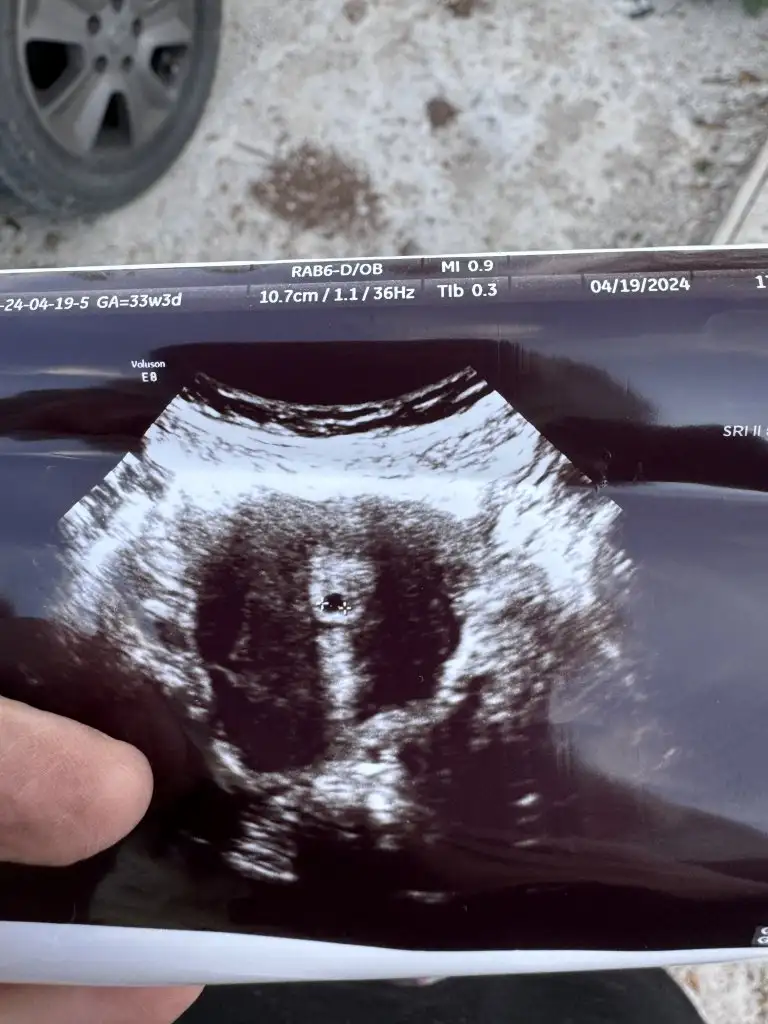

Aynı durum benim başıma geldi kan <1.20 alttaki de ultrason fotoğrafı 5+2 dedi

IMG_3645.jpeg

Aynı durum benim başıma geldi kan <1.20 alttaki de usta fotoğrafı 5+2 dedi

img_3645-jpeg.3416921

Senin kesen var ama kuzucum yukarıdakinde görünmüyordu kese başka bir yerde daha ver tahlil belki yanlışlık vardır

Fotoğrafta minicik bir kese görüyorum. Kan tahlili yanlış belki de evde gebelik testi yapsan aslında ben de merak ettim durumunu şimdi çok garip